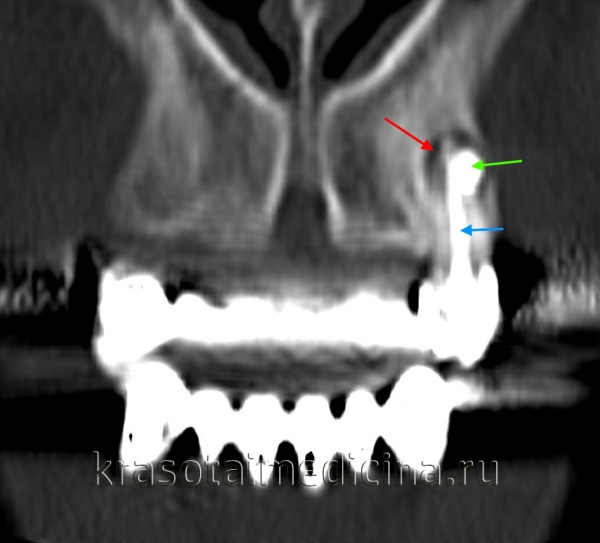

КТ челюстно-лицевой области. Радикулярная киста (красная стрелка) вблизи корня левого клыка верхней челюсти, состояние после эндодонтического лечения (синяя стрелка – филлер в корневом канале), избыток филлера за пределами верхушки зуба (зеленая стрелка).